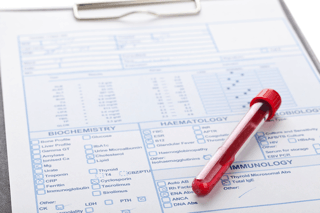

Have you ever had obvious health symptoms but your lab tests come back normal? Many such patients, the majority of them women, are told it’s simply stress, aging, or depression. The problem is most doctors use lab ranges on blood tests when functional ranges provide more clues that explain the symptoms. The lab ranges on a blood test look for diseases while functional medicine ranges look for patterns and markers that spot trends toward disease that can still be reversed or halted. For instance, the lab ranges for diabetes are quite high, but a functional range can let you know...